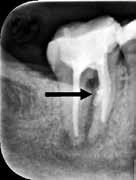

Fig. 2. Tidligere behandlet tand med insufficient eller helt manglende rodfyldning i kanalerne. A. Præmolarer i overkæben med tre insufficiente rodfyldninger og efterfølgende restaurering med stiftopbygning og krone. Desuden første molar uden synlig rodfyldning, men med restaurering, der inddrager pulpakammeret. B. Første molar i overkæben, som kun har synlig rodfyldning i den palatinale kanal. C. Insufficient rodfyldning eller overset rodkanal i første molar i overkæben.

Fig. 2. Previously treated tooth with no or inadequate root filling in canals. A. Maxillary premolars with 3 roots inadequately filled and restored with post and crown. Maxillary first molar with no visible root filling with restoration in pulp chamber and coronal restoration. B. Maxillary first molar with visible root filling only in the palatal canal. C. Inadequate root filling or missed root canal in maxillary first molar.

peroperative faktorer. En af dem er manglende behandling af en rodkanal, enten fordi den ikke blev fundet, eller fordi tandlægen ikke ledte efter den (Fig. 2A-C) (8,9). Det er påvist, at apikal parodontitis forekommer hyppigere i tænder med mindst én ubehandlet eller overset rodkanal (10). Accidentelle perforationer fører ofte til ekstraktion af tanden, men kan almindeligvis undgås med fornuftige endodontiske arbejdsgange (11). Ufuldstændig instrumentering eller forsegling af rodkanalen enten som følge af forkert rodmål eller på grund af fx instrumentfraktur, hyldedannelse eller overinstrumentering af den apikale konstriktion kan føre til, at infektionen persisterer. Rodfile kan frakturere som følge af cyklisk træthedsbrud eller vridningsbelastningsbrud, og incidensraten for brud ligger på 1 % (12). Det sted i tandsættet, der oftest giver anledning til instrumentfraktur, er den apikale del af en mesiofacial rodkanal i en molar (Fig. 3). Kraftig afbøjning af kanalen forøger risikoen for, at filen frakturerer (13). En for kort rodfyldning (> 2 mm fra radiologisk apex) har ligesom overfyldning med guttaperka en nedsat succesrate (14).